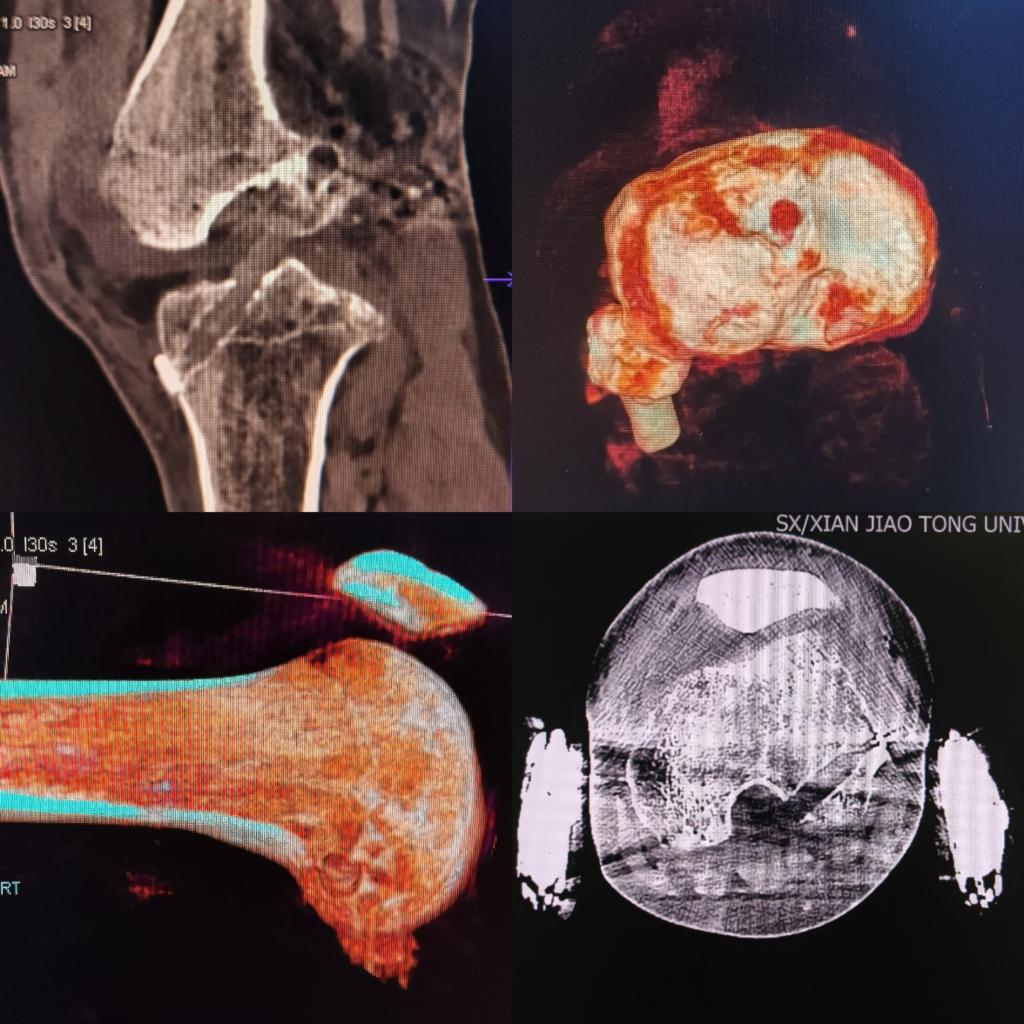

术后复查CT

术后复查核磁

术后复查X线